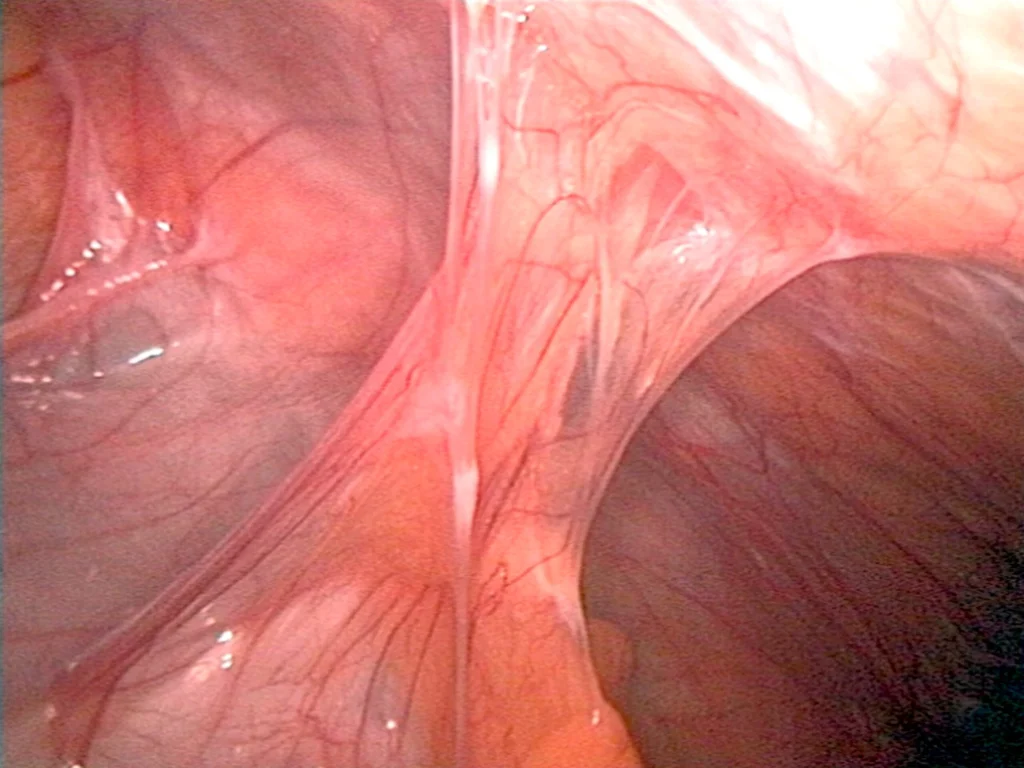

Laparoscopic image showing thin, transparent, fibrous bands of endometriosis-related adhesions connecting pelvic organs. The adhesions appear stretched and vascular, consistent with inflammatory endometriosis tissue rather than simple post-surgical scar tissue.

Pelvic and abdominal adhesions are bands of scar-like tissue that cause organs or tissues to stick together abnormally. While adhesions can form after infection or surgery, endometriosis is now recognized as the most common cause. Unlike post-surgical adhesions—which are typically made of fibrous scar tissue alone—endometriosis adhesions contain active glands, stroma, inflammation, and fibrosis, making them more complex, more painful, and more likely to distort pelvic anatomy. These adhesions can involve the ovaries, uterus, bowel, bladder, pelvic sidewalls, and more, often contributing to chronic pelvic pain, infertility, and organ dysfunction.